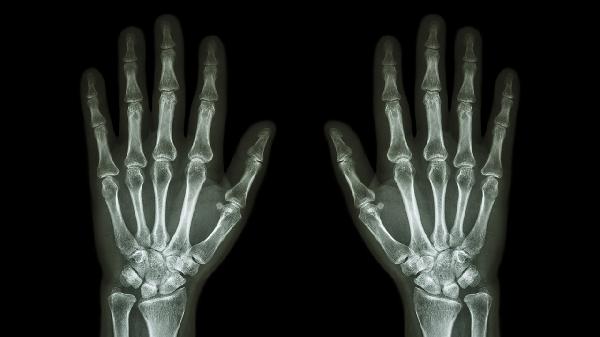

跌打损伤引起的肌肉拉伤、韧带扭伤等软组织损伤,早期表现为局部肿胀瘀斑。祛风骨痛巴布膏中的活血成分可促进淤血消散,应在受伤48小时后贴敷。急性期应冷敷处理,严重者需拍摄X线片排除骨折,必要时使用洛索洛芬钠贴剂加强镇痛。